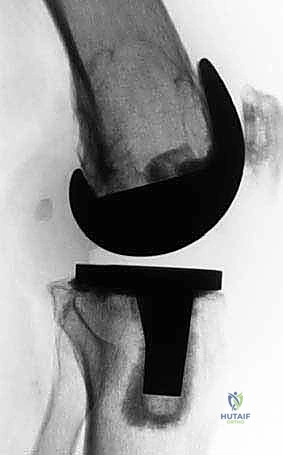

لفهم مدى تعقيد جراحة المراجعة، يجب أولاً فهم تشريح الركبة. يتكون مفصل الركبة من التقاء عظم الفخذ (Femur) مع عظم الساق (Tibia) والرضفة (Patella). الجزء السفلي من عظم الفخذ، والمعروف باللقمتين الفخذيتين (Femoral Condyles)، هو الهيكل الأساسي الذي يتحمل وزن الجسم ويسمح بحركة الانثناء والانبساط.

في الجراحة الأولية، يتم قطع جزء بسيط من هذا العظم لتلبيس المفصل الصناعي. ولكن عند فشل المفصل، يحدث تدمير للبنية العظمية (Metaphysis and Epiphysis)، مما يفقد المفصل الجديد نقاط الارتكاز الأساسية. استعادة "خط المفصل الطبيعي" (Joint Line) هو السر وراء نجاح جراحة المراجعة، وهو ما يتطلب مهارة استثنائية من الجراح لتعويض هذا النقص العظمي بدقة مليمترية.

1. الدعامات المعدنية المعيارية (Modular Metal Augments)

تُستخدم في حالات فقدان العظم من النوع الثاني (AORI Type 2). وهي عبارة عن كتل معدنية (غالباً من التيتانيوم) تأتي بأحجام وسماكات مختلفة (5 ملم، 10 ملم، 15 ملم). يتم تثبيتها بمسامير أو أسمنت عظمي في الجزء الخلفي أو السفلي من المفصل الصناعي لتعويض الفجوات العظمية واستعادة خط المفصل بدقة.

الخطوة 4: إعادة البناء (Reconstruction & Augmentation)

هنا يتم تطبيق التقنيات المذكورة (الدعامات، المخاريط، أو الطعوم). يقوم الجراح بتجربة مفصل مؤقت (Trial) للتأكد من استعادة خط المفصل، توازن الأربطة (Ligament Balancing)، والمدى الحركي للركبة.

الخطوة 5: التثبيت النهائي (Final Implantation)

يتم تثبيت المفصل النهائي المعقد (Revision Prosthesis) باستخدام أسمنت عظمي مخصص يحتوي على مضادات حيوية، مع التأكد من التوافق الميكانيكي الحيوي التام.